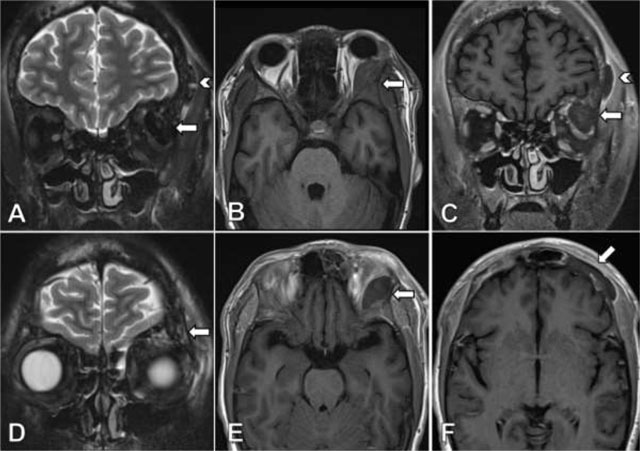

Figure 2

Coronal TSE T2-weighted image with fat suppression (A) shows a markedly hypointense lesion located in the lateral aspect of the left orbital roof (arrow) and a second lesion lining the external table of the frontal bone on the left side (arrow head). On axial TSE T1-weighted images (B) the lesion exhibits a isointense signal compared to the adjacent bone, without lesional enhancement after injection of gadolinium (E). Coronal contrast-enhanced TSE T1-weighted image (C) reveals a faint perilesional enhancement, more prominently in the lesion lining the frontal bone on the left (arrow head). Coronal TSE T2-weighted image with fat suppression (D) shows asymmetrical, discrete bone edema and prominent nonenhancing lesions on contrast-enhanced TSE T1-weighted image (F) in the frontal bone on the left side compared to the right side.